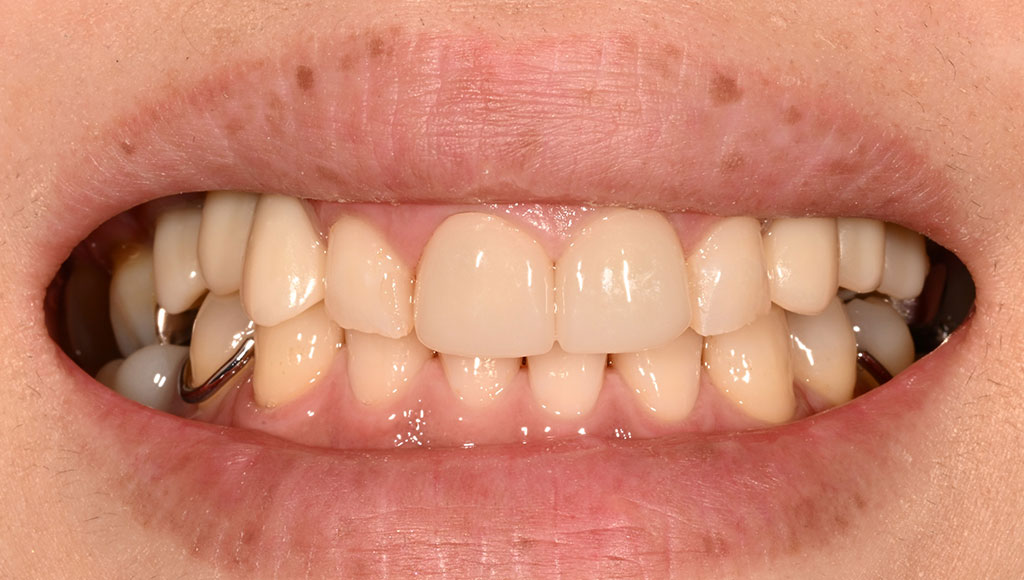

After2

患者様の主訴

40代女性。横浜市在住。左上1番右上1番のクラウンに着色があり審美的に問題を抱えていたため、ご来院されました。

診断結果

ジルコニアクラウンを装着するために元のブリッジを外し、歯の形成を行いジルコニアクラウンをセット

治療内容

ジルコニアクラウンを装着するために元のクラウンを外し、歯の形成を行い光学印象(プライムスキャンによる)型取りを行いました。光学印象のデータを元に当院の院内技工室にてデジタル加工を行い、ジルコニアクラウンを作成し、セットを行いました。

治療期間

2回

治療費用

総額:330,000円(税込)

◼️内訳

ジルコニアクラウン(前歯):150,000円(税込)/1本×2本

光学印象(プライムスキャン)

リスク・副作用

補綴物の脱落・欠落、咬合違和感、色調補正